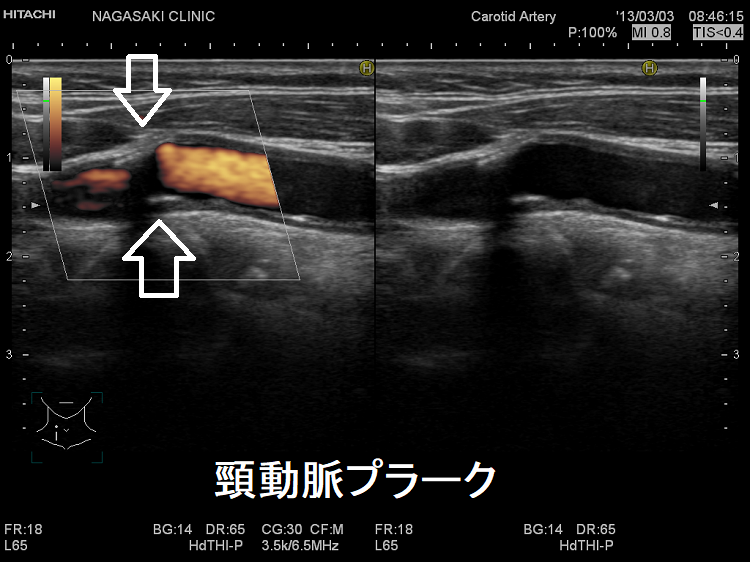

動脈硬化が進んだ血管にはプラーク(コレステロールエステルを大量に含んだ脂質の塊)(矢印)ができて、血管内が狭くなります。血管エコーでプラークを探す。動脈硬化した血管は硬くもろいため、大動脈では血圧に負けて大動脈瘤になることがあります(急性大動脈解離・大動脈瘤)。

(↓)デジタルハイビジョン超音波装置で見たプラーク。